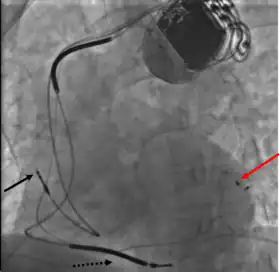

Permanent transvenous pacing

Permanent pacing with an implantable pacemaker involves transvenous placement of one or more pacing electrodes within a chamber, or chambers, of the heart, while the pacemaker is implanted under the skin below the clavicle. The procedure is performed by incision of a suitable vein into which the electrode lead is inserted and passed along the vein, through the valve of the heart, until positioned in the chamber. The procedure is facilitated by fluoroscopy which enables the physician to view the passage of the electrode lead. After satisfactory lodgement of the electrode is confirmed, the opposite end of the electrode lead is connected to the pacemaker generator.

CRT devices have at least two leads, one passing through the vena cava and the right atrium into the right ventricle to stimulate the septum, and another passing through the vena cava and the right atrium and inserted through the coronary sinus to pace the epicardial wall of the left ventricle. Often, for patients in normal sinus rhythm, there is also a lead in the right atrium to facilitate synchrony with the atrial contraction. Thus, the timing between the atrial and ventricular contractions, as well as between the septal and lateral walls of the left ventricle can be adjusted to achieve optimal cardiac function.

A pacemaker may be implanted whilst a person is awake using local anesthetic to numb the skin with or without sedation, or asleep using a general anesthetic.[25] An antibiotic is usually given to reduce the risk of infection.[25] Pacemakers are generally implanted in the front of the chest in the region of the left or right shoulder. The skin is prepared by clipping or shaving any hair over the implant site before cleaning the skin with a disinfectant such as chlorhexidine. An incision is made below the collar bone and a space or pocket is created under the skin to house the pacemaker generator. This pocket is usually created just above the pectoralis major muscle (prepectoral), but in some cases the device may be inserted beneath the muscle (submuscular).[26] The lead or leads are fed into the heart through a large vein guided by X-ray imaging (fluoroscopy). The tips of the leads may be positioned within the right ventricle, the right atrium, or the coronary sinus, depending on the type of pacemaker required.[25] Surgery is typically completed within 30 to 90 minutes. Following implantation, the surgical wound should be kept clean and dry until it has healed. Some movements of the shoulder within a few weeks of insertion carry a risk of dislodging the pacemaker leads.[25]